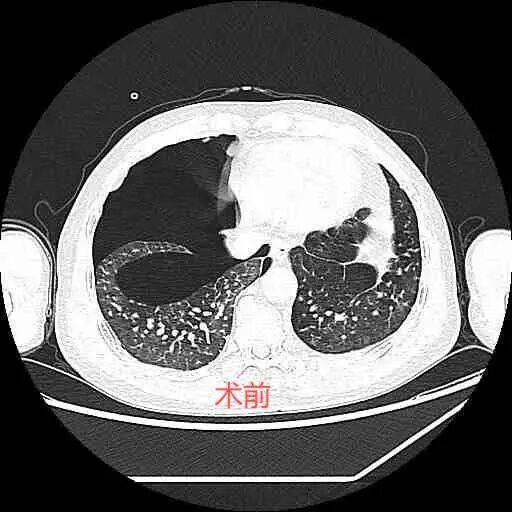

53歲的患者李某長期從事粉塵作業(yè),因突發(fā)右側(cè)胸悶痛入院治療。經(jīng)診斷為“右側(cè)氣胸、塵肺”,雖經(jīng)傳統(tǒng)胸腔閉式引流治療十余日,仍持續(xù)存在氣泡溢出癥狀,肺組織難以復(fù)張,嚴(yán)重影響了他的呼吸功能和生活質(zhì)量。“這類難治性氣胸以往需轉(zhuǎn)外科手術(shù),但患者塵肺體質(zhì)手術(shù)風(fēng)險極高?!焙粑c危重癥醫(yī)學(xué)科主任宋彬醫(yī)師介紹,醫(yī)療團隊采用SBO技術(shù),通過支氣管鏡精準(zhǔn)定位漏氣點,注入患者自體血液混合制劑,成功實現(xiàn)微創(chuàng)封堵。

治療后,患者術(shù)后第一天,水封瓶氣泡明顯減少,第二天水封瓶未見水柱波動,第三天復(fù)查胸部CT提示氣胸明顯吸收,右肺復(fù)張,隨后患者康復(fù)出院。